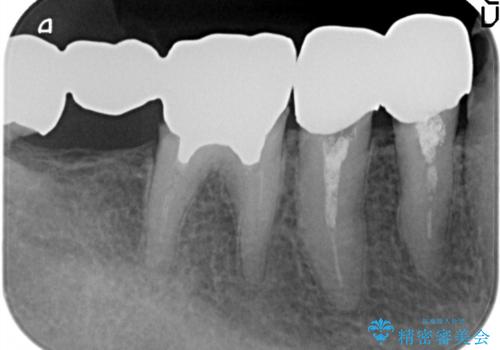

多数の銀歯と虫歯、セラミック・インプラント治療

- 銀歯だらけの口腔内を全てきっちり治療したい、と希望され来院されました。

検査の結果、残すことの難しい歯をインプラントに置き換え、残すことのできる歯は虫歯の徹底的な除去後にセラミック治療を行っていくこととしました。

- 125万円(インプラント×2・チタンカスタムアバットメント×2・ジルコニアクラウン×4・仮歯×4)費用は治療当時の料金となります